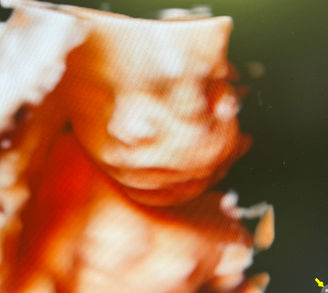

Gallery